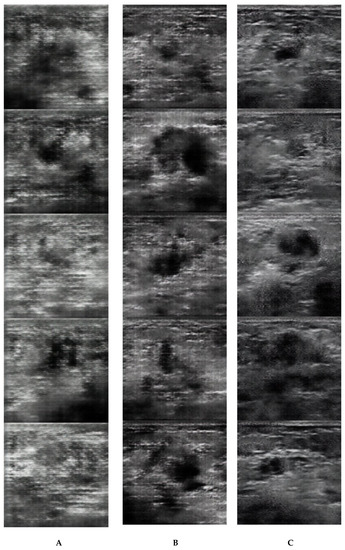

3. Results